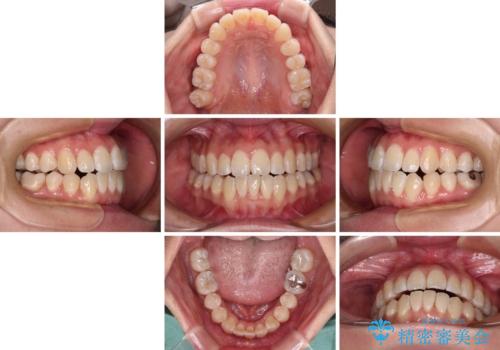

- 上下前歯の隙間と、外側を向いていて歯磨きのしにくい奥歯を気にして来院された患者様です。

下顎前歯が1本欠損しており、上下アーチはアンバランスとなりますが、インビザラインを用いて上下の隙間を改善しながら歯列を整えることとしました。

外側を向いている奥歯は、内側にアンカースクリューを埋入して牽引の固定ゲント氏、部分的にワイヤー装置を用いることで歯列に納めることとしました。

下顎前歯の1本欠損により左右の咬合が不安定となり、治療経過で噛みにくい状態が続きましたが、最終的には違和感なく噛めるようになりました。